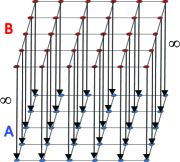

Metrication error: Metrication error, also known as grid bias, is defined as the artifacts which appear in graph-based segmentation methods due to penalizing region boundaries only across axis aligned edges. ¡ltx:note¿Figure 3 compares the discrete and continuous version of a max-flow algorithm. As seen in Figure 3, the contours obtained by graph cuts are noticeably blocky in the areas with weak regional cues (weak data term), while the contours obtained by the continuous method are smooth.¡/ltx:note¿ The discrete nature of graph-based methods makes it difficult to efficiently implement a convex regularizer like total variation in the discrete domain. Metrication error can be reduced in graph-based methods by increasing the graph connectivity, e.g. (Boykov and Kolmogorov, 2003), but that also increases memory usage and computation time. In contrast, within the continuous domain, there is no such limitation and regularizers can be implemented efficiently that makes the PDE approaches free from metrication error. Note that although approaches with continuous energy formulations do not induce metrication errors, due to the discrete nature of digital images, all continuous operations are estimated by their discrete versions in the implementation stage.

(a) GF

(b) CCMF

(c)

(d)

(e)

(f) Figure 3: ¡ltx:note¿Metrication artifacts. Brain segmentation using (a) classical max-flow algorithm or graph cuts (GC) and (b) combinatorial continuous max-flow (CCMF) (Couprie et al., 2011). (c,e) Zoomed regions of (a). (d,f) Zoomed regions of (b).

(Images adopted from (Couprie et al., 2011))¡/ltx:note¿ -